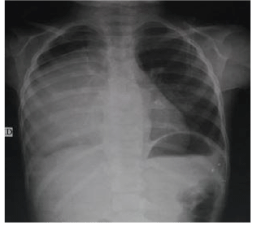

Giantmediastinalganglio neuroma in a female child

Yasser A.El Sayed1*, Moh.Fathy2, Moh.Salem3, Alaa Eisa4, Ashraf Enait5, Kerolos Emad6, Bothinah A.Al Haseeb7, Mona Atef8

We report an eight year female patient admitted to the department of pediatrics at Abbasia Pulmonary Hospital at Cairo, Egypt. The child was complaining of pain on the right lower chest and upper abdome.